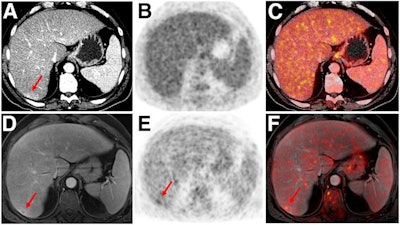

Indeterminate lesion on PET/CT classified by PET/MRI for 53-year-old man with lung cancer. Contrast-enhanced CT (A), PET (B), and fused F-18 FDG PET/CT (C) images are displayed in comparison with contrast-enhanced T1-weighted MRI (D), PET (E), and fused F-18 FDG PET/MRI (F) images. In CT (A), hyperdense, subcentimeter liver lesion (arrows) in segment VII is suggestive of transient hepatic attenuation difference or small hemangioma. As malignancy cannot be excluded, it needs further investigation. On PET/MRI, lesion is clearly classified as metastasis because of contrast enhancement and tracer uptake due to later acquisition time point. Follow-up CT confirmed diagnosis after 78 days. Image courtesy of the Journal of Nuclear Medicine.

Indeterminate lesion on PET/CT classified by PET/MRI for 53-year-old man with lung cancer. Contrast-enhanced CT (A), PET (B), and fused F-18 FDG PET/CT (C) images are displayed in comparison with contrast-enhanced T1-weighted MRI (D), PET (E), and fused F-18 FDG PET/MRI (F) images. In CT (A), hyperdense, subcentimeter liver lesion (arrows) in segment VII is suggestive of transient hepatic attenuation difference or small hemangioma. As malignancy cannot be excluded, it needs further investigation. On PET/MRI, lesion is clearly classified as metastasis because of contrast enhancement and tracer uptake due to later acquisition time point. Follow-up CT confirmed diagnosis after 78 days. Image courtesy of the Journal of Nuclear Medicine.After exclusions, the researchers examined 1,003 PET/MRI scans of 918 patients. PET/MRI outperformed PET/CT in terms of providing more tumor information (26.3%), mostly in patients with malignant bone disease, followed by lung cancer, prostate cancer, and gynecologic or breast cancer. PET/MRI identified additional malignant findings in 5.3% of cases, which lead to a change in tumor, node, and metastases (TNM) staging in 2.9% of cases. PET/MRI also clearly classified indeterminate PET/CT lesions in 11% of cases.